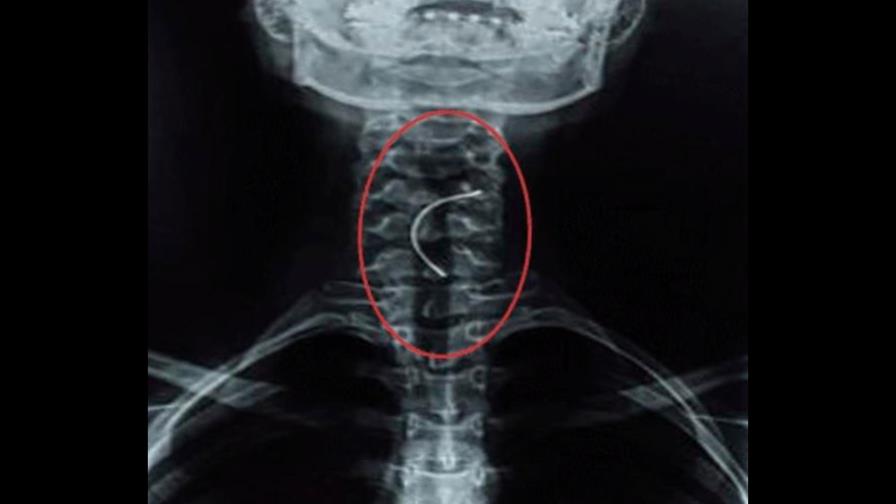

Una joven de 15 años sufrió un terrible accidente luego de tragarse el expansor de paladar, que usaba para su tratamiento de ortodoncia, mientras almorzaba en su vivienda de Paraguay.

Sin embargo, cuando las esperanzas se estaban acabando, la joven vomitó y el objeto subió hasta su garganta, tras esta acción los médicos realizaron una nueva radiografía y dijeron que con una endoscopía podrían sacar el expansor.

La menor fue sometida al proceso quirúrgico y la operación salió exitosa. Actualmente, se recupera favorablemente en el Instituto Nacional de Enfermedades Respiratorias y del Ambiente Juan Max Bohener (Ineram).